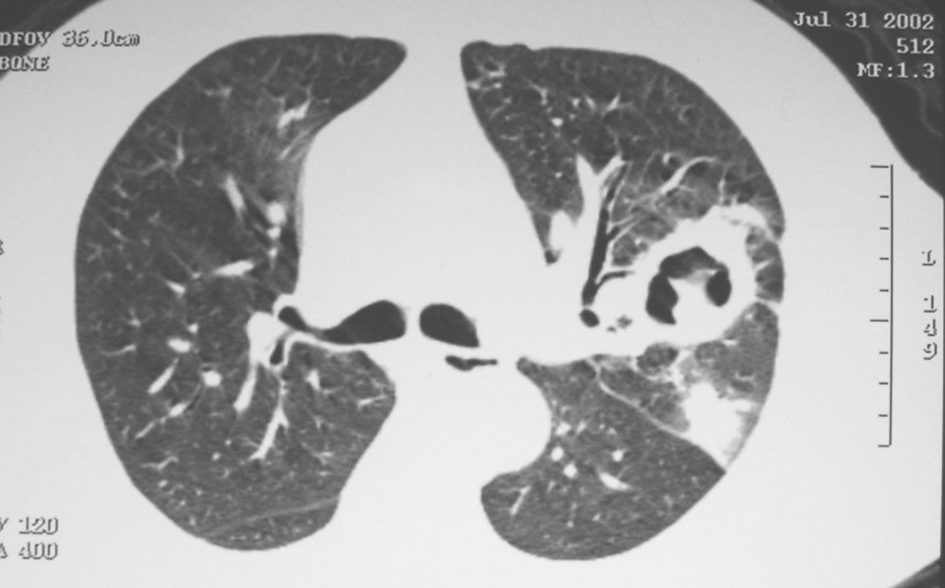

气管及双侧各叶段支气管未见明显异常。于右上叶后段行经支气管肺活检及右肺中叶支气管肺泡灌洗检查。肺组织活检示少量支气管黏膜,可见干酪样坏死,坏死周围呈慢性肉芽肿性炎症反应,抗酸染色阳性(图7)。BALF经分枝杆菌培养/药敏系统培养出分枝杆菌,并通过基因检测确定为结核分枝杆菌。

图7 经支气管肺活检

活检肺组织中可见干酪样坏死(A.HE染色,200×),抗酸染色见大量结核分枝杆菌(B.抗酸染色,1000×)

最后诊断:双肺继发性肺结核。

临床确诊后,给予3HRZE/9HRE抗结核治疗,1年后复查胸部CT,示双肺原结节样病灶明显吸收(图8)。